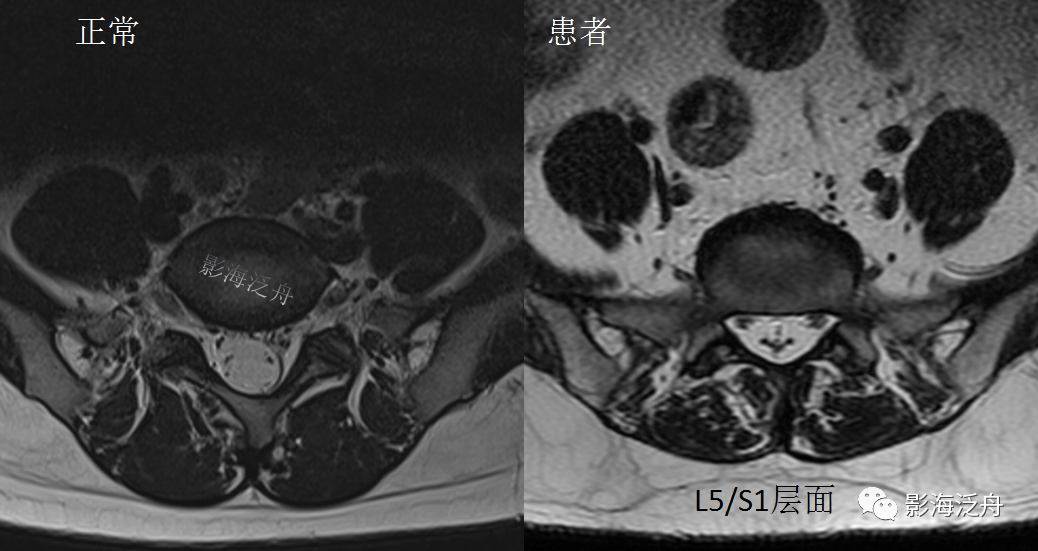

正常的腰骶部MR解剖:一般情况下,L5/S1层面是常规腰椎MR平扫横断位的最后一层,如上图所示,硬膜囊(红箭头)外只有很少量的脂肪(黄箭头)分布,马尾神经由硬膜囊内(绿箭)穿出并沿椎间孔区向外走行(蓝箭)。硬膜囊内的马尾神经均匀分散在硬膜囊边缘区。

开篇那个患者的L5/S1水平横断面图像:可见椎管内大部分空间被脂肪组织占据(黄箭头),硬膜囊显著受压呈“V字”形改变(红箭头),硬膜囊内的马尾神经聚拢在一起显示不清。